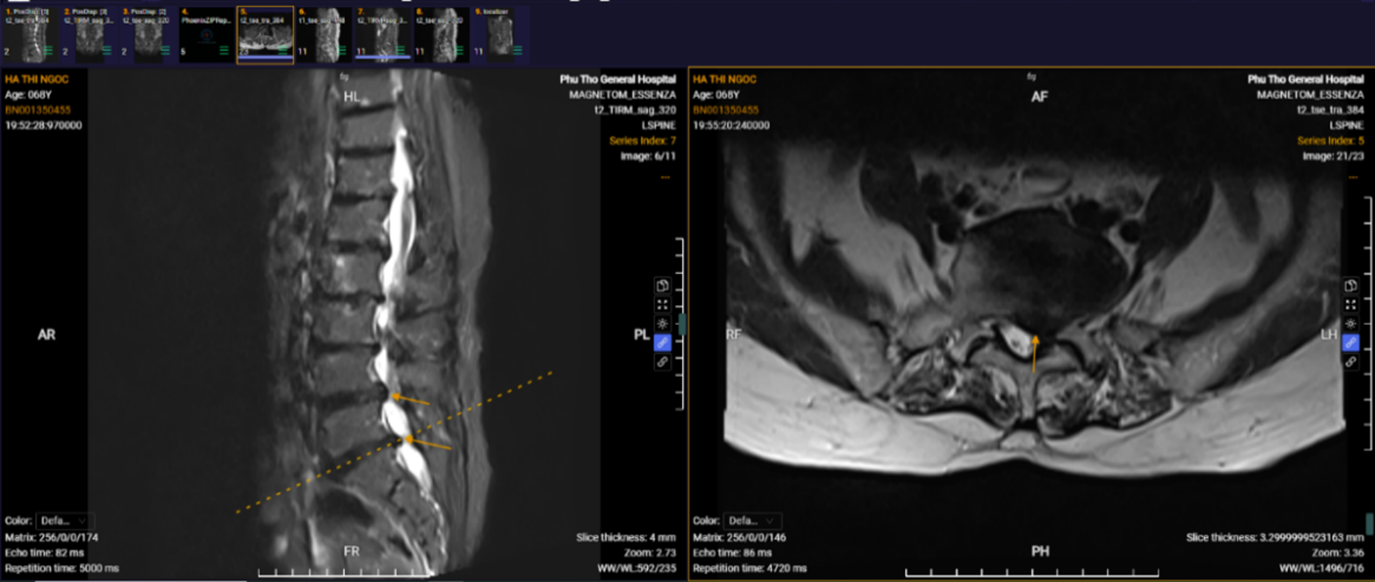

Hình ảnh phim chụp của người bệnh Hà Thị Ngọc khi vào viện.

Hơn 20 năm chịu đựng những cơn đau lưng hành hạ, phục hồi chỉ sau 10 ngày phẫu thuật là trường hợp của người bệnh Hà Thị Ngọc, trú tại phường Thanh Miếu, tỉnh Phú Thọ. Người bệnh nhập viện trong tình trạng đau thắt lưng kéo dài, đau lan xuống hai chân và cả tay trái, kèm tê bì nhiều. “Có những lúc tôi cảm thấy cơ thể đau nhức như bị hàng nghìn mũi kim châm chích. Dù đã điều trị theo nhiều phương pháp nhưng chỉ đỡ được một thời gian rồi lại đau lại”.